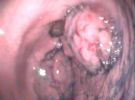

2.腺瘤性息肉系來源於胃黏膜上皮的良性胃腫瘤,約占胃息肉的10%~25%。一般體積較大,呈球形或半球形,多數無蒂,表面光滑,少數呈扁平狀、條狀或分葉狀。組織學上主要由表面上皮、小凹上皮和腺體增生形成。上皮分化不成熟,核分裂象多見,可分為管狀、絨毛狀及混合型腺瘤,常伴有明顯腸化生和異型增生。息肉間質為疏鬆結締組織,有少量淋巴細胞浸潤。黏膜肌層無明顯增生,肌纖維無分散現象。本型息肉癌變率高,可達30%~58.3%,尤其瘤體直徑大於2cm、絨毛狀腺瘤、異型增生Ⅲ度者惡變率更高。

胃息肉胃息肉很少有陽性體徵,合併炎症時上腹部可有壓痛,出血多者有繼發性貧血表現。X線胃鋇餐透視和胃鏡檢查是診斷胃息肉的主要方法。X線胃鋇餐透視顯示胃腔內呈現圓形或半圓形邊界整齊清晰,表面平整的充盈缺損,多數在1cm左右大小,有蒂者可見其移動。胃鏡檢查對診斷實屬必要,鏡下可見胃壁黏膜上有圓形或半圓形隆,一般小於2cm。邊界清晰,表面光滑平整,色澤呈正常黏膜象或呈鮮紅色,質地柔軟,有蒂或無蒂,單發或多發。部分息肉呈菜花狀表現,其表面或有糜爛或有潰瘍。菜花狀息肉和體積大於2cm者有惡變之可能,活組織病理檢查有助於鑑別診斷。